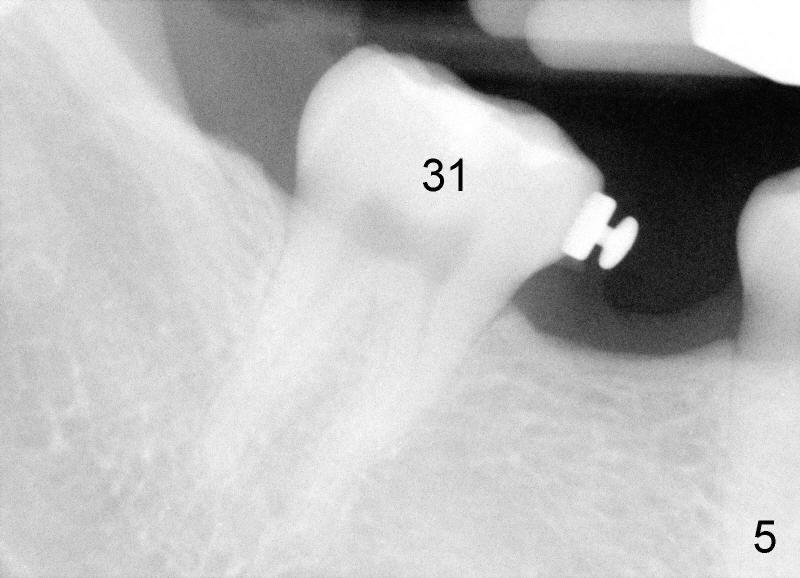

Small incision is made in the retromolar area. Pilot drill is used before a 10 mm Ancor Pro Mini-implant is placed (Orthoorganizer). But it is too loose. Incision is extended distally. With shallower pilot drilling, the next placement of mini is stable (Fig.2). With placement of lingual button on the mesial aspect of #31 and power chain (Fig.2,5), the journey of distalization begins. But it is not so easy as expected.

The tooth #31 is uprighted in six months (Fig.8, as compared to Fig.5). The edentulous space increases from 6 mm to 9 mm mesiodistally, which is still not enough. The M-D width of #19 is 12 mm. In fact, the tooth #2 has been intruded substantially (Fig.9. Compare to Fig.3). The possible reason for resistance of distal movement of #31 is an interference from the tooth #3 (Fig.10). A regular implant is placed intentionally in the distal aspect of the edentulous area (Fig.11: I). The next plan is to place temporary crown on the implant once it osteointegrates to raise the occlusion efficiently so that the tooth #31 is free to move distally with retraction of power chain attached to the mini-implant (as shown in Fig.2). The regular implant may be also used as anchorage to push #31 distally. See you later.